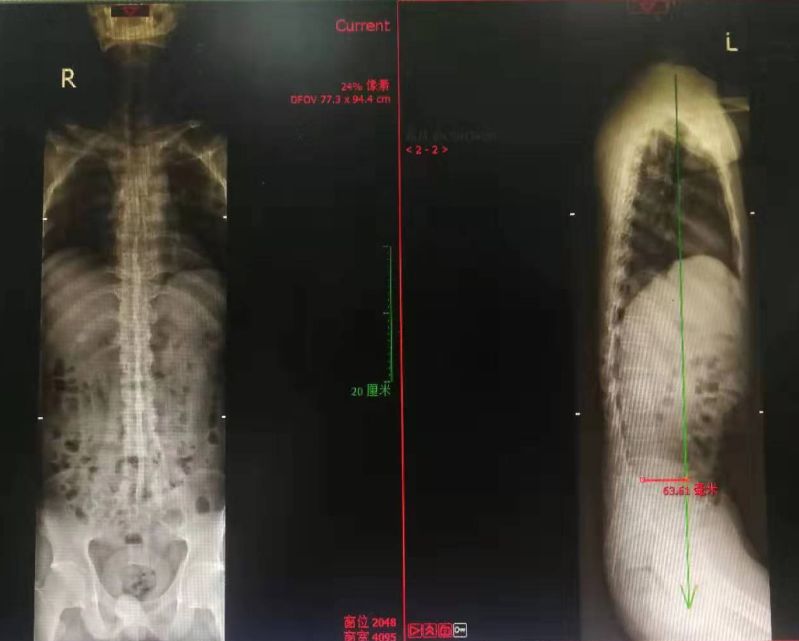

深圳市中医院骨三科的何升华主任经过仔细的检查、看片以后得出诊断结论:病人为强直性脊柱炎合并L1、L2椎体爆裂骨折。

全脊柱正侧位显示骶髂关节间隙消失

脊柱竹节样融合改变

腰椎MRI及CT显示腰1 腰2椎体新鲜压缩骨折